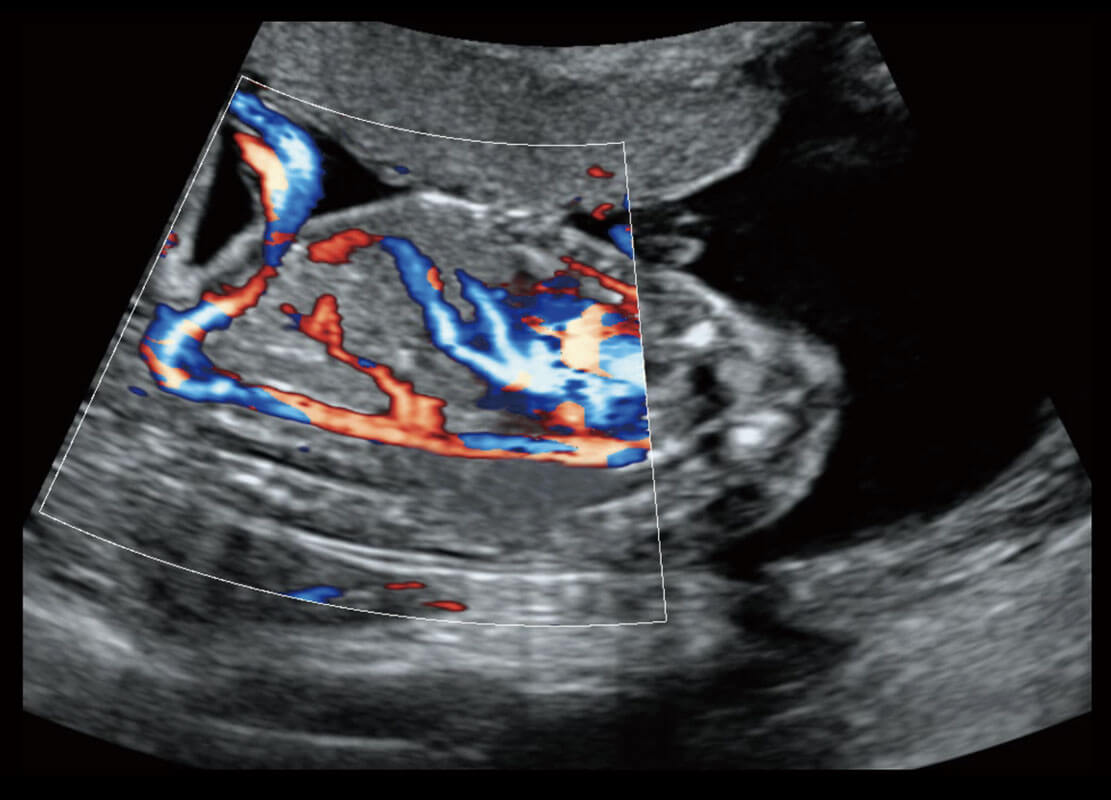

P60搭载一系列胎儿心脏成像技术,实现精细的胎儿心脏评估。

四腔切面

四腔心血流

右室双出口

胎心容积成像